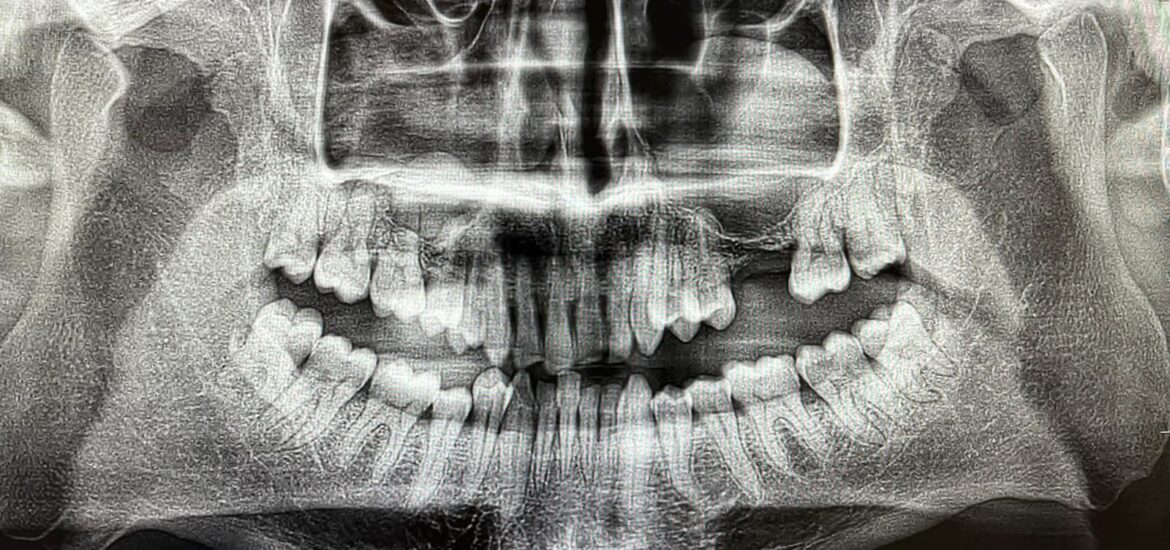

Dr. Antonio Vázquez interviene con una rinoplastia a Carlos, un paciente de 20 años con problemas respiratorios.

Este tipo de cirugía, que se utiliza también para corregir defectos de nacimiento o causados por un accidente, también subsana problemas de respiración nasal. La nariz es el órgano donde comienza la respiración y está situada en una zona crítica de la cara, en el que cualquier defecto estético se aprecia a primera vista.

La percepción de estos defectos estéticos es personal y ante un mismo defecto una persona puede demandar cirugía y otra no. La corrección estética debe ir asociada a mejorar la funcionalidad de la nariz. La intervención se realiza bien por incisiones internas o externas dependiendo del caso, que permiten manejar las estructuras internas para su corrección.